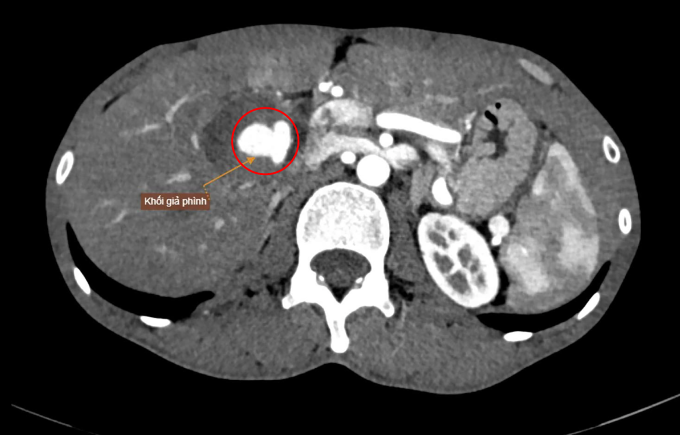

Kết quả chụp CT ổ bụng có tiêm thuốc cản quang của anh Thời tại Bệnh viện Đa khoa Tâm Anh TP HCM cho thấy nhiều túi giả phình mạch máu tại các vị trí như động mạch gan, vùng dạ dày, thận, thắt lưng. Trong đó, một khối giả phình lớn nằm tại vùng rốn gan, xuất phát từ nhánh động mạch gan phải, kích thước 40×40×65 mm chèn ép các cấu trúc lân cận, gây rối loạn tưới máu nhu mô gan và đè ép tĩnh mạch thận phải.

Khối giả phình lớn nguy cơ vỡ trên hình chụp CT. Ảnh: Bệnh viện Đa khoa Tâm Anh